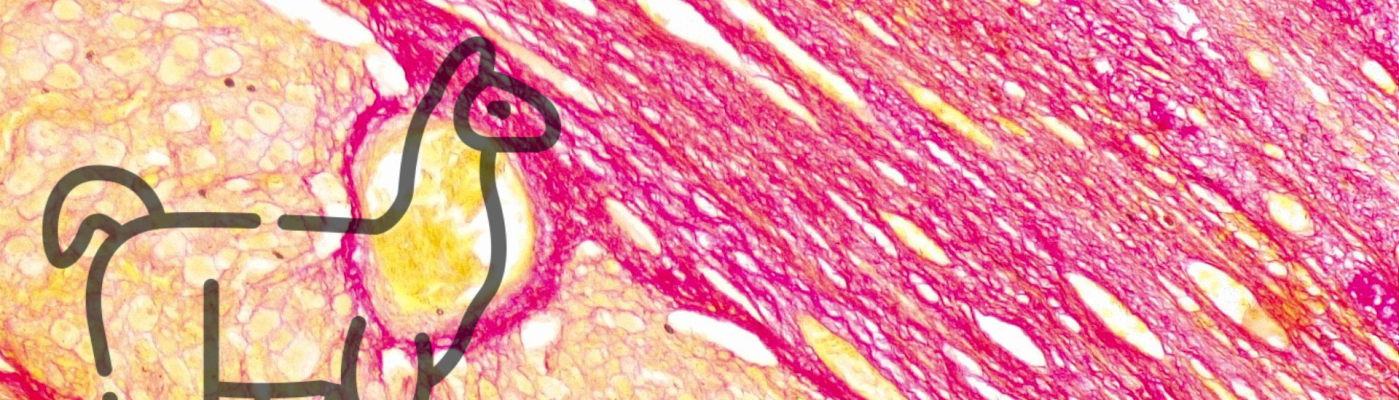

La curiosidad nos llevó a hacer cortes histológicos y coloraciones con hematoxilina-eosina para ver la estructura y picrosirius red para ver la presencia de colágeno. Con los cortes nos pudimos acercar al diagnóstico de quiste folicular (hasta donde entendemos, claro). Sin embargo, hay que destacar que lo debería ver alguien que haga patología para asegurar el diagnóstico. Como esto fue por pura curiosidad, nos quedaremos con nuestro presuntivo.